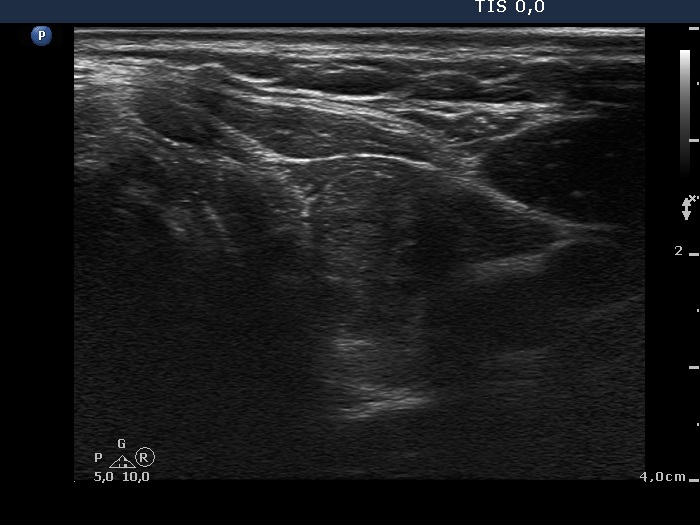

Discrete lesion or nodule in Hashimoto's thyroiditis - case 1 (1615) (ultrasonographic picture 4)

Left lobe, transverse view. There is an echonormal, inhomogeneous discrete lesion in the hypoechogenic lobe.